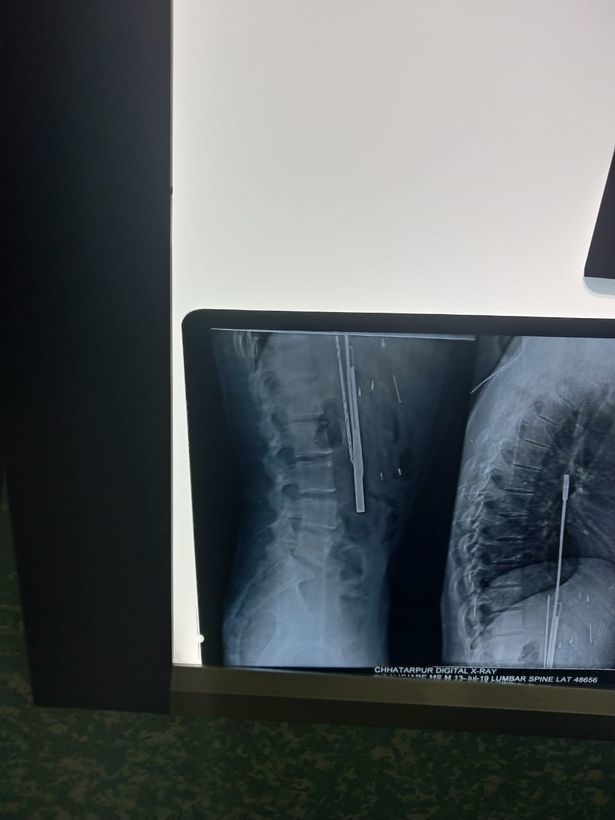

![]() |

| Một phim chụp X-quang cho thấy các vật thể găm trong bụng anh Thakur |